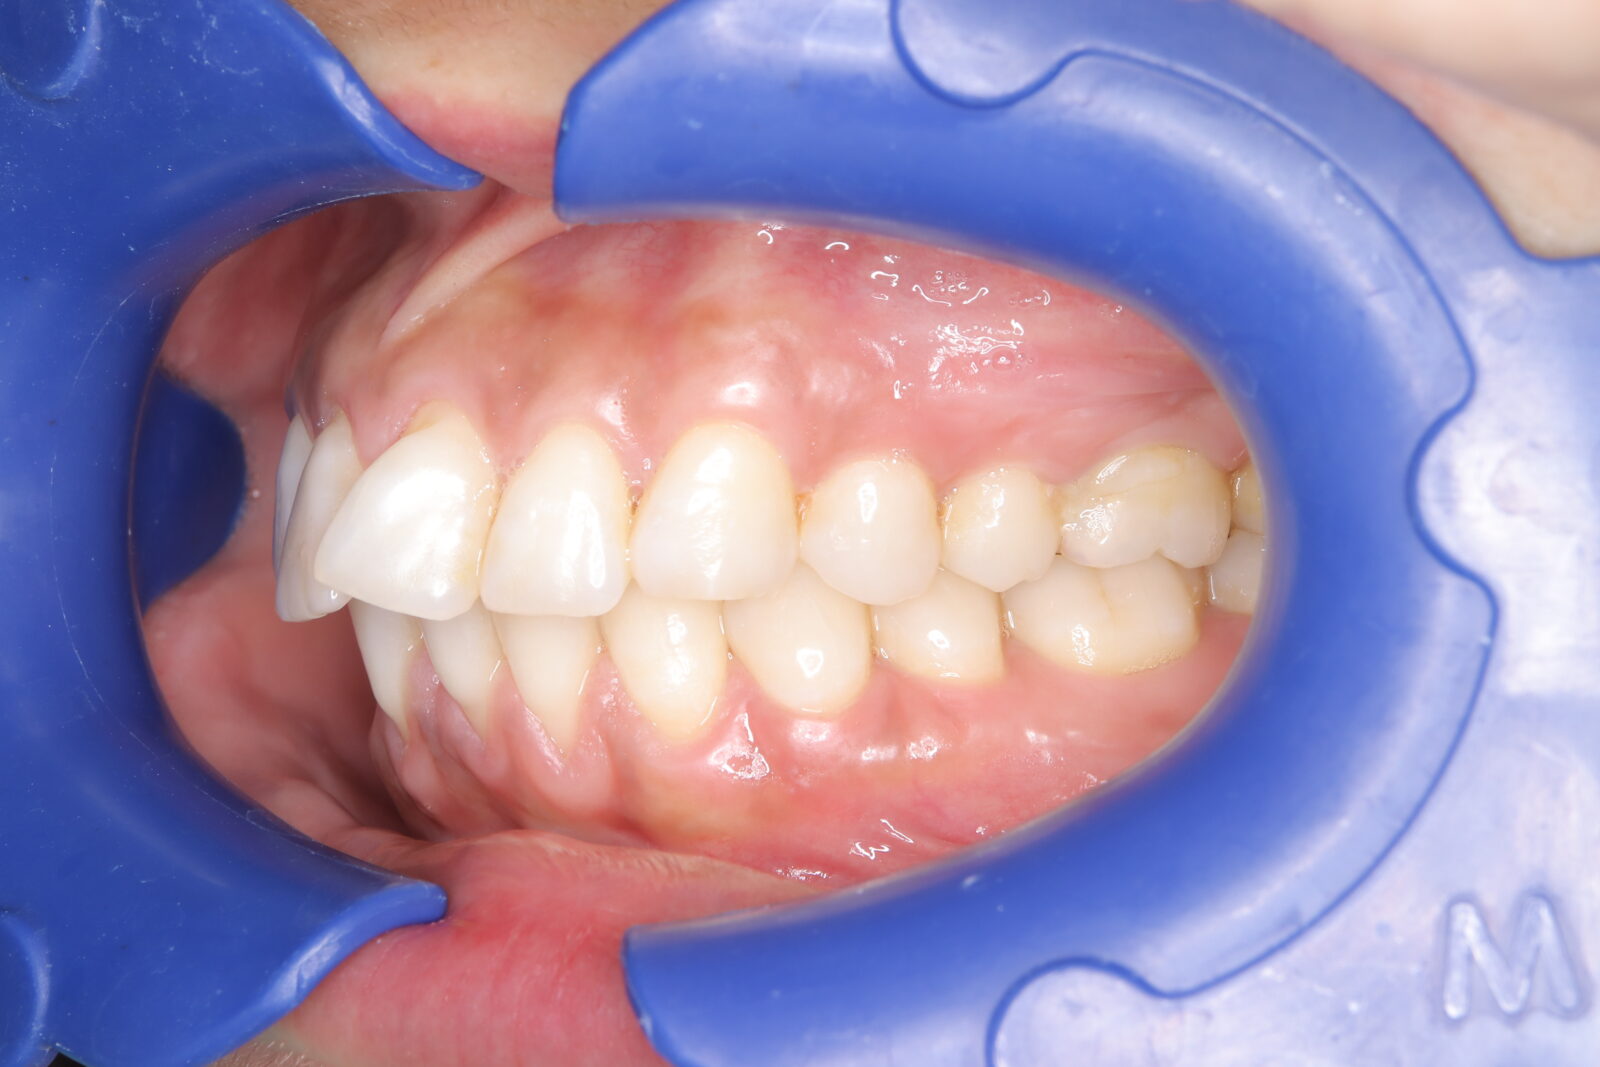

インビザライン(全体矯正)+ホワイトニングコースの症例

典型的な出っ歯だったが、インビザラインとホワイトニングでコンプレックスを改善。

・費用:935,000円(税込)

・治療期間:14ヶ月

・通院回数:14回

・34歳女性

-リスクと副作用-

・長時間マウスピースを装着するため、むし歯や歯周病のリスクがある。治療後はリテーナーを装着しないと後戻りしてしまうリスクがある。

・ホワイトニング剤の影響で知覚過敏が起こる可能性がある。色が徐々に戻る可能性がる。